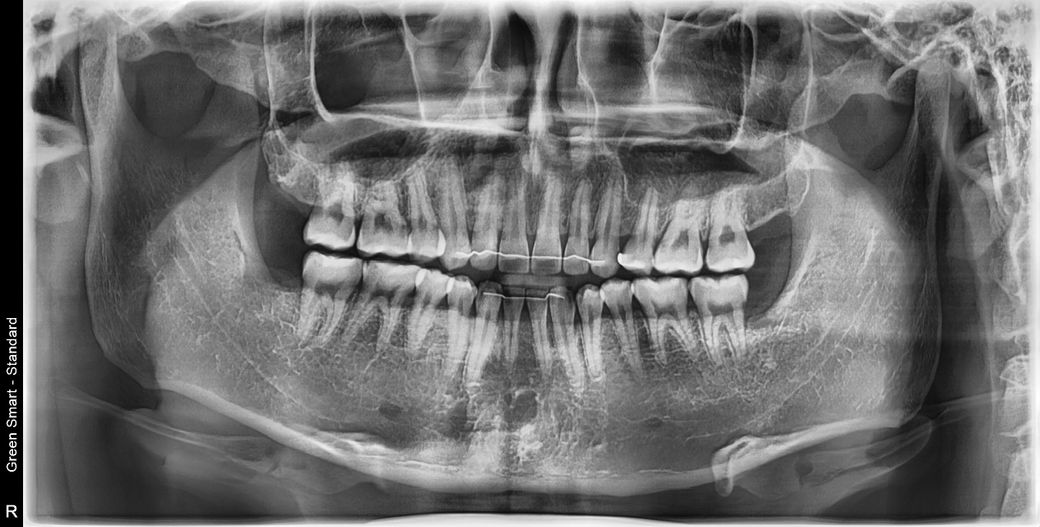

충치/크랙 과잉진단 의심돼서 여쭙습니다..

이갈이가 있고 10년전 제1 소구치 위에만 발치교정했습니다

문제가 된다고 지적받은 치아는

16,17,26,27

두번째가 깨진 부분들 다 인접면 충치라고 그러던데 다른치과에서 찍은 교익 방사선,파노라마,사진들 모두(각자 다른 치과) 고려했을때 법랑질 뚫고 간 흔적이 안보여서 판독 부탁드리려고 합니다

5/30(휴대폰 겹친 검은음영 참고부탁드립니다..)

3. 사진상으로 추가적으로 확인해봐야할 치아는 #16, #25, #26, #36, #46 입니다